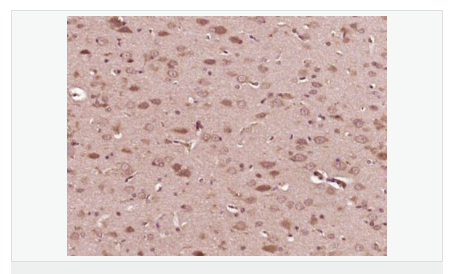

| 產品應用 | WB=1:500-2000 ELISA=1:5000-10000 IHC-P=1:100-500 IHC-F=1:100-500 Flow-Cyt=2ug/Test ICC=1:100-500 IF=1:100-500 (石蠟切片需做抗原修復) not yet tested in other applications. optimal dilutions/concentrations should be determined by the end user. |

| 產品介紹 | Converts sphingomyelin to ceramide. Also has phospholipase C activities toward 1,2-diacylglycerolphosphocholine and 1,2-diacylglycerolphosphoglycerol. Isoform 2 and isoform 3 have lost catalytic activity. Involvement in disease: Defects in SMPD1 are the cause of Niemann-Pick disease type A (NPDA) ; also known as Niemann-Pick disease classical infantile form. It is an early-onset lysosomal storage disorder caused by failure to hydrolyze sphingomyelin to ceramide. It results in the accumulation of sphingomyelin and other metabolically related lipids in reticuloendothelial and other cell types throughout the body, leading to cell death. Niemann-Pick disease type A is a primarily neurodegenerative disorder characterized by onset within the first year of life, mental retardation, digestive disorders, failure to thrive, major hepatosplenomegaly, and severe neurologic symptoms. The severe neurological disorders and pulmonary infections lead to an early death, often around the age of four. Clinical features are variable. A phenotypic continuum exists between type A (basic neurovisceral) and type B (purely visceral) forms of Niemann-Pick disease, and the intermediate types encompass a cluster of variants combining clinical features of both types A and B. Function: Converts sphingomyelin to ceramide. Also has phospholipase C activities toward 1,2-diacylglycerolphosphocholine and 1,2-diacylglycerolphosphoglycerol. Isoform 2 and isoform 3 have lost catalytic activity. Subunit: Monomer. Subcellular Location: Lysosome. DISEASE: Defects in SMPD1 are the cause of Niemann-Pick disease type A (NPDA) [MIM:257200]; also known as Niemann-Pick disease classical infantile form. It is an early-onset lysosomal storage disorder caused by failure to hydrolyze sphingomyelin to ceramide. It results in the accumulation of sphingomyelin and other metabolically related lipids in reticuloendothelial and other cell types throughout the body, leading to cell death. Niemann-Pick disease type A is a primarily neurodegenerative disorder characterized by onset within the first year of life, mental retardation, digestive disorders, failure to thrive, major hepatosplenomegaly, and severe neurologic symptoms. The severe neurological disorders and pulmonary infections lead to an early death, often around the age of four. Clinical features are variable. A phenotypic continuum exists between type A (basic neurovisceral) and type B (purely visceral) forms of Niemann-Pick disease, and the intermediate types encompass a cluster of variants combining clinical features of both types A and B. Defects in SMPD1 are the cause of Niemann-Pick disease type B (NPDB) [MIM:607616]; also known as Niemann-Pick disease visceral form. It is a late-onset lysosomal storage disorder caused by failure to hydrolyze sphingomyelin to ceramide. It results in the accumulation of sphingomyelin and other metabolically related lipids in reticuloendothelial and other cell types throughout the body, leading to cell death. Clinical signs involve only visceral organs. The most constant sign is hepatosplenomegaly which can be associated with pulmonary symptoms. Patients remain free of neurologic manifestations. However, a phenotypic continuum exists between type A (basic neurovisceral) and type B (purely visceral) forms of Niemann-Pick disease, and the intermediate types encompass a cluster of variants combining clinical features of both types A and B. In Niemann-Pick disease type B, onset of the first symptoms occurs in early childhood and patients can survive into adulthood. Similarity: Belongs to the acid sphingomyelinase family. Contains 1 saposin B-type domain. SWISS: P17405 Gene ID: 6609 Database links: Entrez Gene: 100720041 Guinea pig Entrez Gene: 6609 Human Entrez Gene: 20597 Mouse Entrez Gene: 100353898 Rabbit Omim: 607608 Human SwissProt: P17405 Human SwissProt: Q04519 Mouse Unigene: 498173 Human Unigene: 4628 Mouse Unigene: 485064 Mouse Unigene: 18277 Rat Important Note: This product as supplied is intended for research use only, not for use in human, therapeutic or diagnostic applications. ASM酸性神經鞘磷脂酶是ASMase神經鞘磷脂酶最重要的一個亞型,是細胞膜的重要組成成分。ASM在細胞凋亡、調節腫瘤細胞生長、參與Fas信號系統傳遞等方面均可發揮重要作用。 |